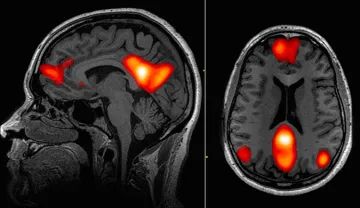

与无意识反应相比,当某人被要求“假装”时,其大脑活动似乎也存在差异。在一个小型实验中,研究人员使用正电子发射断层扫描仪(PET)研究了12名健康受试者,以测量其大脑各部分的代谢活动。在一组测试中,受试者被要求假装无法移动腿部。在另一组测试中,相同的受试者被催眠并被暗示他们的腿已经瘫痪。脑成像研究显示,在这两种情况下,被激活的大脑区域有所不同。

后来的一项研究进一步探讨了催眠与假装的问题,这次使用了核磁共振扫描仪,该扫描仪能在观察软组织时提供更多细节。这一次,研究人员发现,受试者的运动皮层——大脑中控制身体运动的区域——在催眠状态下会被激活。这表明被催眠的人确实在尝试移动肢体,尽管结果都一样,他们并没有比假装肢体瘫痪的人做出更多的运动。

斯皮格尔说,在大脑的突显网络(包括前脑岛和前扣带回皮层的脑区,这一区域可以调控我们的主观感受,译者注)中可以找到部分答案。该网络帮助我们识别值得关注的周围环境——从时时刻刻充斥着我们大脑的大量感官数据中筛选出相关信息。在一项实验中,斯皮格尔和其同事催眠了高度可催眠和低度可催眠的受试者,同时扫描了他们的大脑。催眠过程中,高度可催眠人群的突显网络活跃度更低。斯皮格尔说:“当这种情况发生时,你对其他可能发生的事情就不那么担心了。它允许你与世界的其他部分断开连接。”

(www.ncbi.nlm.nih.gov/pmc/articles/PMC4365296/)

特胡恩说,最有力的证据来自于大脑的默认模式网络(default mode network,DMN)——休息时最活跃的大脑区域。他说:“人们认为该网络与自相关心理活动有着密切联系,如白日梦、走神等。”

特别是内侧前额皮层(该网络的一部分)被认为在催眠中起着至关重要的作用。特胡恩说:“这一区域似乎与自相关处理、元认知(对认知的认知)以及控制自己思想的能力有关。这些都是在催眠诱导下可能被抑制的过程。”

由于默认模式网络的活跃度暂时受损,人们可能很难将自己视为有意识的个体。这可能是你对自己的身体没有完全自主权的特殊感觉的根源。